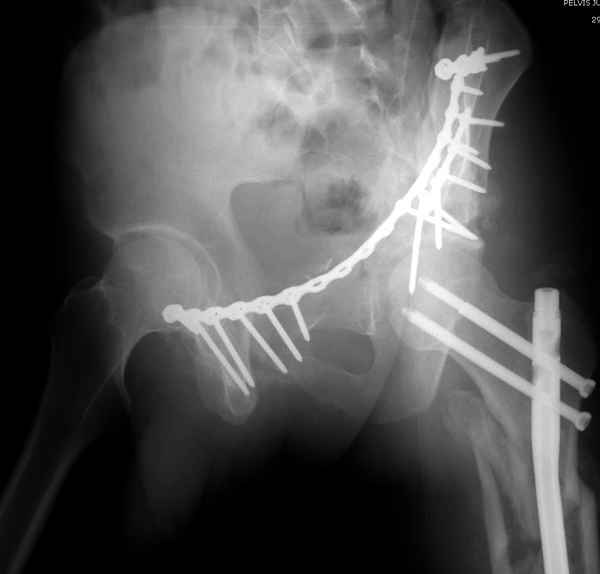

высылаю дополнительно сканы.

Когда перелом не получается отнести к какому либо типу - эффективнее всего описать более детально. В дальнейшем проще бывает сортировать, и что важнее - "руководство к действию" бывает более обоснованным. В данном случае графа клинического диагноза может выглядеть так: Застарелый разрыв правого крестцово-подвздошного сочленения, консолидирующиеся со смещением переломы крыла и тела правой подвздошной кости, обеих колонн и задней гемисферы правой вертлужной впадины. Состояние после остеосинтеза.

>Застарелый разрыв правого крестцово-подвздошного сочленения, консолидирующиеся со смещением переломы крыла и тела правой подвздошной кости, обеих колонн и задней гемисферы правой вертлужной впадины. Состояние после остеосинтеза.

Судя по представленным реконструкциям (не очень хорошего качества - много наводок)

мы имеем дело с полупоперечным переломом у которого отломался задний край или его отломали, превратив перелом в полный двухколонный.

По отдельным срезам и тем более по реконструкции трудно судить о сращении крыла и задней колонны с осевым скелетом.

В большинстве случаев при двухколонных переломах

в итоге получается прочный бублик с дыркой. При эндопротезировании в дырку помещается головка, а чашка должна неплохо заклиниться в бублике.

Главное, чтобы бублик не был разорван, что не очень понятно на представленных снимках.

Из того минимума, что представлено, мне кажется, мы имеем дело с двухколонным переломом вертлужной впадины. Обычно медиальный (центральный) "вывих" головки встречаются в сложных двухколонных переломах со смещением.

По-моему, надо готовить больного к будущей артропластике, но без опоры на задний столб невозможно удержать протез. Опорная конструкция (кольца и т.д.) должны иметь опору, и поэтому мы бы сделали реостеосинтез задним доступом. При надобности остеотомия и рутинная фиксация с межколонными винтами.